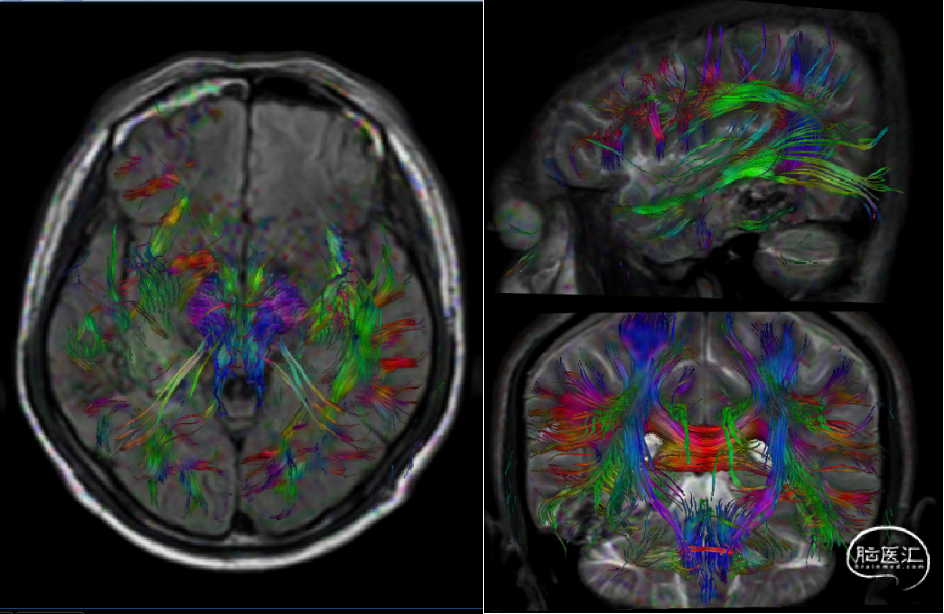

DTI-视辐射

●手术要点及注意事项:术前腰大池引流放液控制颅压,骨窗至中颅窝底,开颅保护Labbe静脉(浅部回流),术中电生理监测,超声判断畸形团边界,复合DSA造影判断AVM切除程度。

患者术后无新发神经功能缺失,视力视野无缺失。

术后MRI

深刻理解AVM畸形团“六面体”构造。该患者颞叶底面(颈外动脉硬膜支供血),颞下回外侧面(薄层脑组织)属于易于显露和控制的界面。